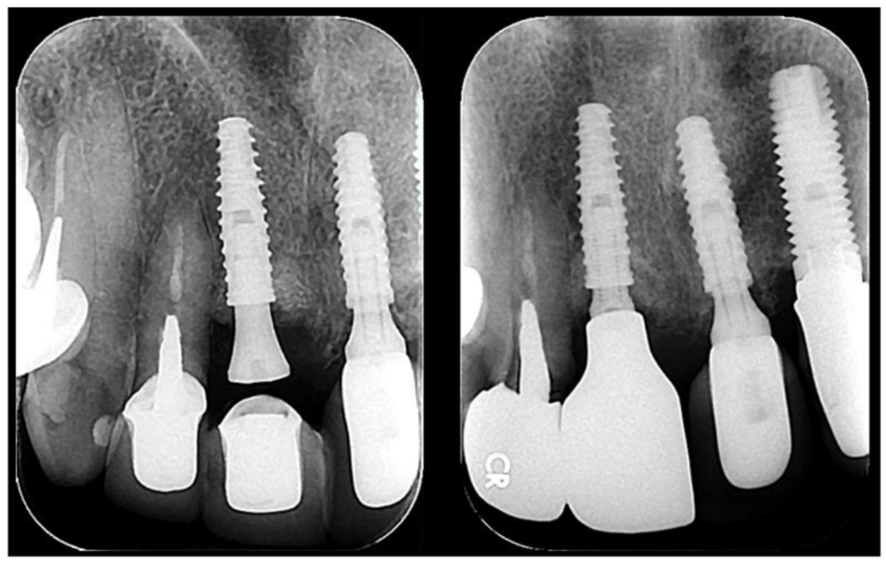

Este caso abre um leque de discussões muito interessantes para a reabilitação anterior superior. O primeiro tópico a questionar seria o motivo de não se ter reabilitado logo os quatro incisivos, haja visto o comprometimento estético da área. A resposta é simples: o paciente não aceitou esta terapia, considerando que seria muito traumático perder quase todos os dentes anteriores de uma só vez. Assim, o caso foi sendo realizado de uma maneira mais conservadora e os implantes foram sendo colocados um a um, ao longo de oito anos, sob a decisão do paciente.

Por fim, vale ressaltar bastante que o espaço mésio-distal da região dos incisivos facilitou a instalação dos implantes e das próteses, sem falar ainda na abundância de mucosa queratinizada que contribuiu diretamente no resultado estético final. Assim, podemos concluir que a utilização de implantes Cone Morse de diâmetro de 3,5 mm e com pilares mais estreitos, favorecem a manutenção do espaço biológico peri-implantar, aumentando a manutenção da saúde e a longevidade dos tecidos duros e moles ao redor dos nossos implantes.